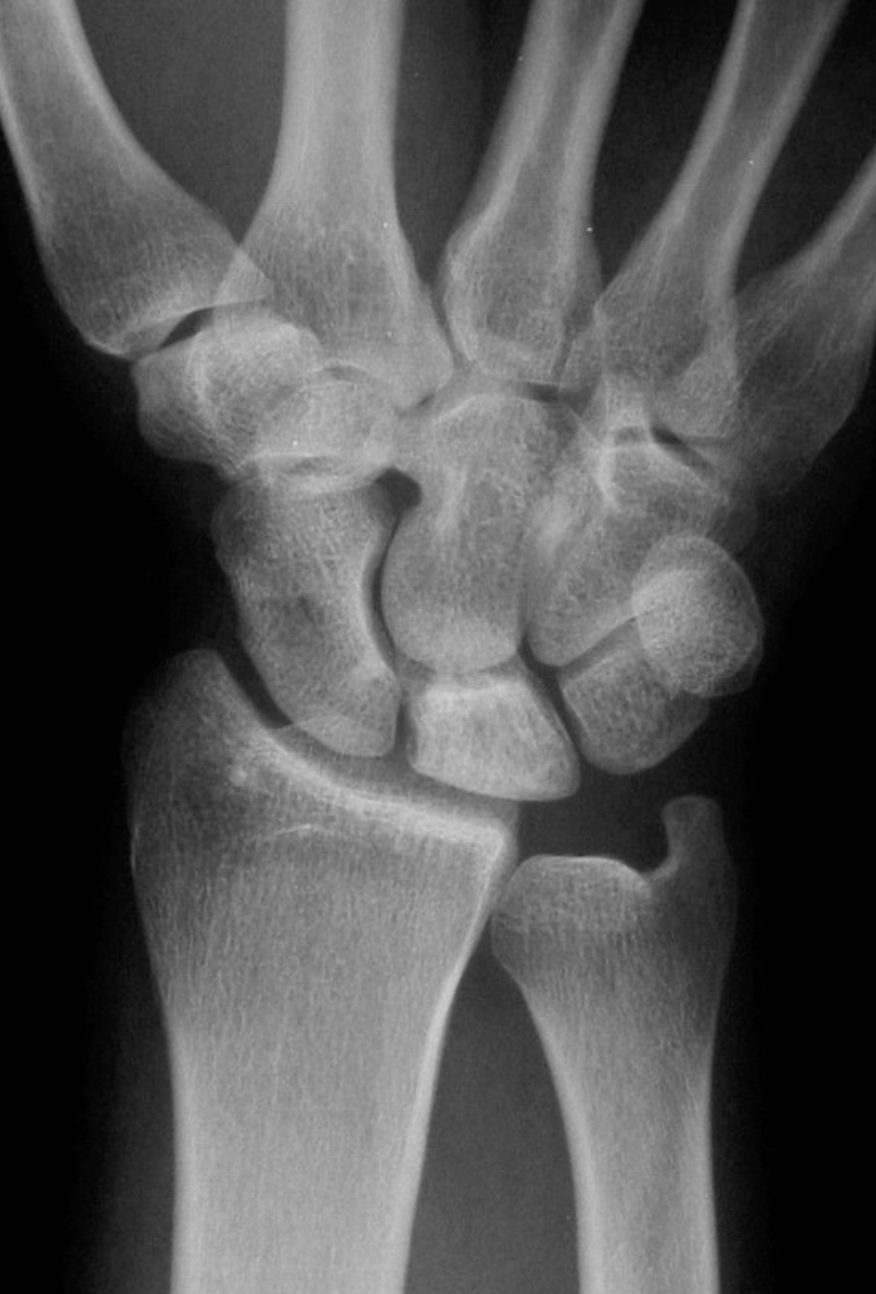

It is actually difficult to determine what will be the natural history of Kienbock’s disease in patients who first present. The condition is sometimes diagnosed very early on, before any xray changes are seen. In other patients the condition presents when the lunate bone fractures or breaks because of bone death.

Kienbock’s disease can be classified according to the changes seen on xrays and scans, and we try to classify the condition in all patients, so that we can give an idea of what is likely to happen. If, for example, a patient presents with stage 2 Kienbock’s, but 6 months later has progressed to stage 3, then we assume that the disease process is active. If no progression of the condition is seen on serial xrays, then we can say that the disease process is static.

At the other end of the spectrum, in some patients the bone seems to collapse and crumble, with the development of osteoarthritis and consequent loss of movement with increased pain.